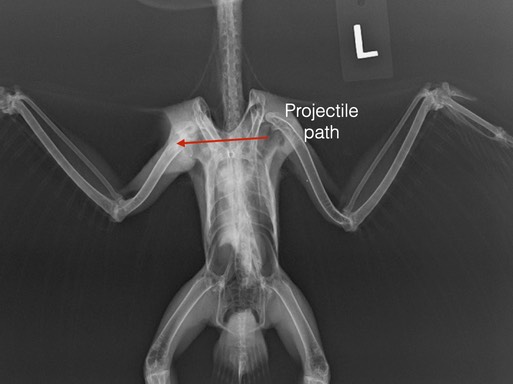

The first was Cooper’s Hawk 20-558 from Haines, OR. The hawk's right humerus and scapula were fractured. We suspected the cause was gunshot, but there were no metal fragments visible on an x-ray and we found only one wound on the right shoulder. A necropsy confirmed the hawk had been shot (likely with non-lead ammunition which does not fragment like lead). There was a small entrance wound on the left side of the back. The wound channel went under the spine, through the right scapula and humerus, exiting at the shoulder.